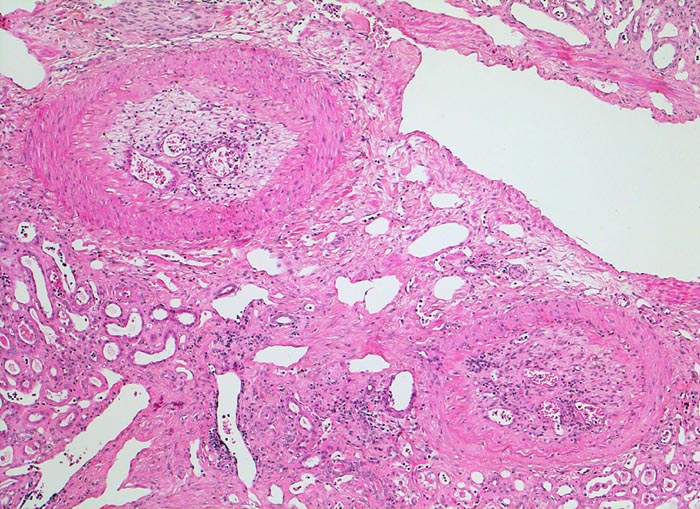

Morphologie:

Je nach Grösse des verschlossenen Gefässes sind unterschiedlich grosse (wenige Millimeter bis mehrere Zentimeter) solitäre oder multiple scharf begrenzte Herde erkennbar. Nach etwa einer Woche imponiert der akute Infarkt als gelber erhabener Bezirk mit 2-5mm breitem rotem Randsaum. Subakute Infarkte bilden flache homogene rote Herde. Nach Monaten bildet sich eine scharf begrenzte weisse Narbe aus. Infolge unterschiedlicher Kollateralversorgung z.B. via Arteria spermatica oder ovarica führt der Verschluss der Arteria renalis nicht immer zur Totalnekrose. Das Endstadium grosser Infarkte bildet die grob gebuckelte Infarkt-Schrumpfniere.

Akute Infarkte bilden histologisch scharf begrenzte kokardenförmig aufgebaute Herde mit zentraler Koagulationsnekrose umgeben von einem Saum neutrophiler Granulozyten. In der Peripherie ist das partiell geschädigte Gewebe ödematös hämorrhagisch und enthält dilatierte hyperämische Gefässe. Die Nekrose wird durch neutrophile Granulozyten und Makrophagen abgebaut und durch Granulationsgewebe ersetzt, welches zu einer gefässarmen Narbe schrumpft. Die äusserste Rindenzone bleibt infolge der Kollateralversorgung durch Kapselgefässe oft vom Infarkt ausgespart. Infarktnarben können wie alle Narben verkalken.